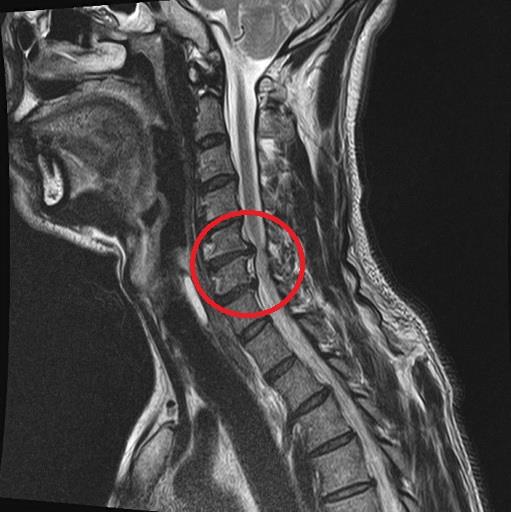

フルヌードですいません。

写真の通り

首のヘルニアが悪化しまして、

右上半身激痛でして、

右手は痺れて不自由でして、

こんな非常事態、初でして、

お客様には大変ご迷惑をおかけします。

早く治ればいいのですが・・・

ちょっと時間がかかりそう・・・(泣)